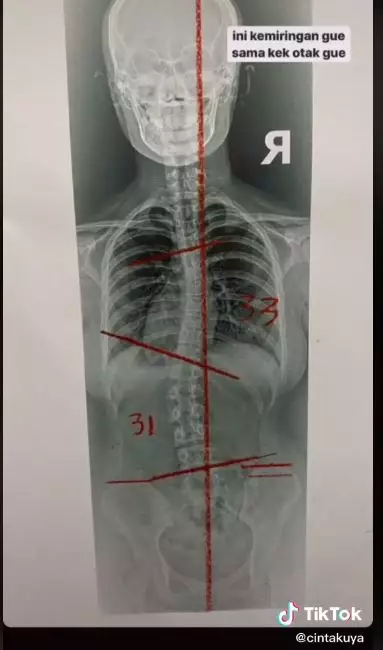

Seperti diketahui, lewat akun TikTok-nya, Cinta Kuya mengaku tak percaya diri dengan skoliosis yang ia idap. Skoliosis sendiri merupakan kelainan tulang belakang yang membuat penderitanya memiliki struktur tulang miring ke arah samping atau melengkung seperti huruf S. Hal tersebut membuat para penderitanya tak terlihat tegak saat berjalan maupun duduk.

2. Melalui hasil rontgen dari dokter, diketahui tingkat kemiringan tulang belakang Cinta sebesar 33 derajat.